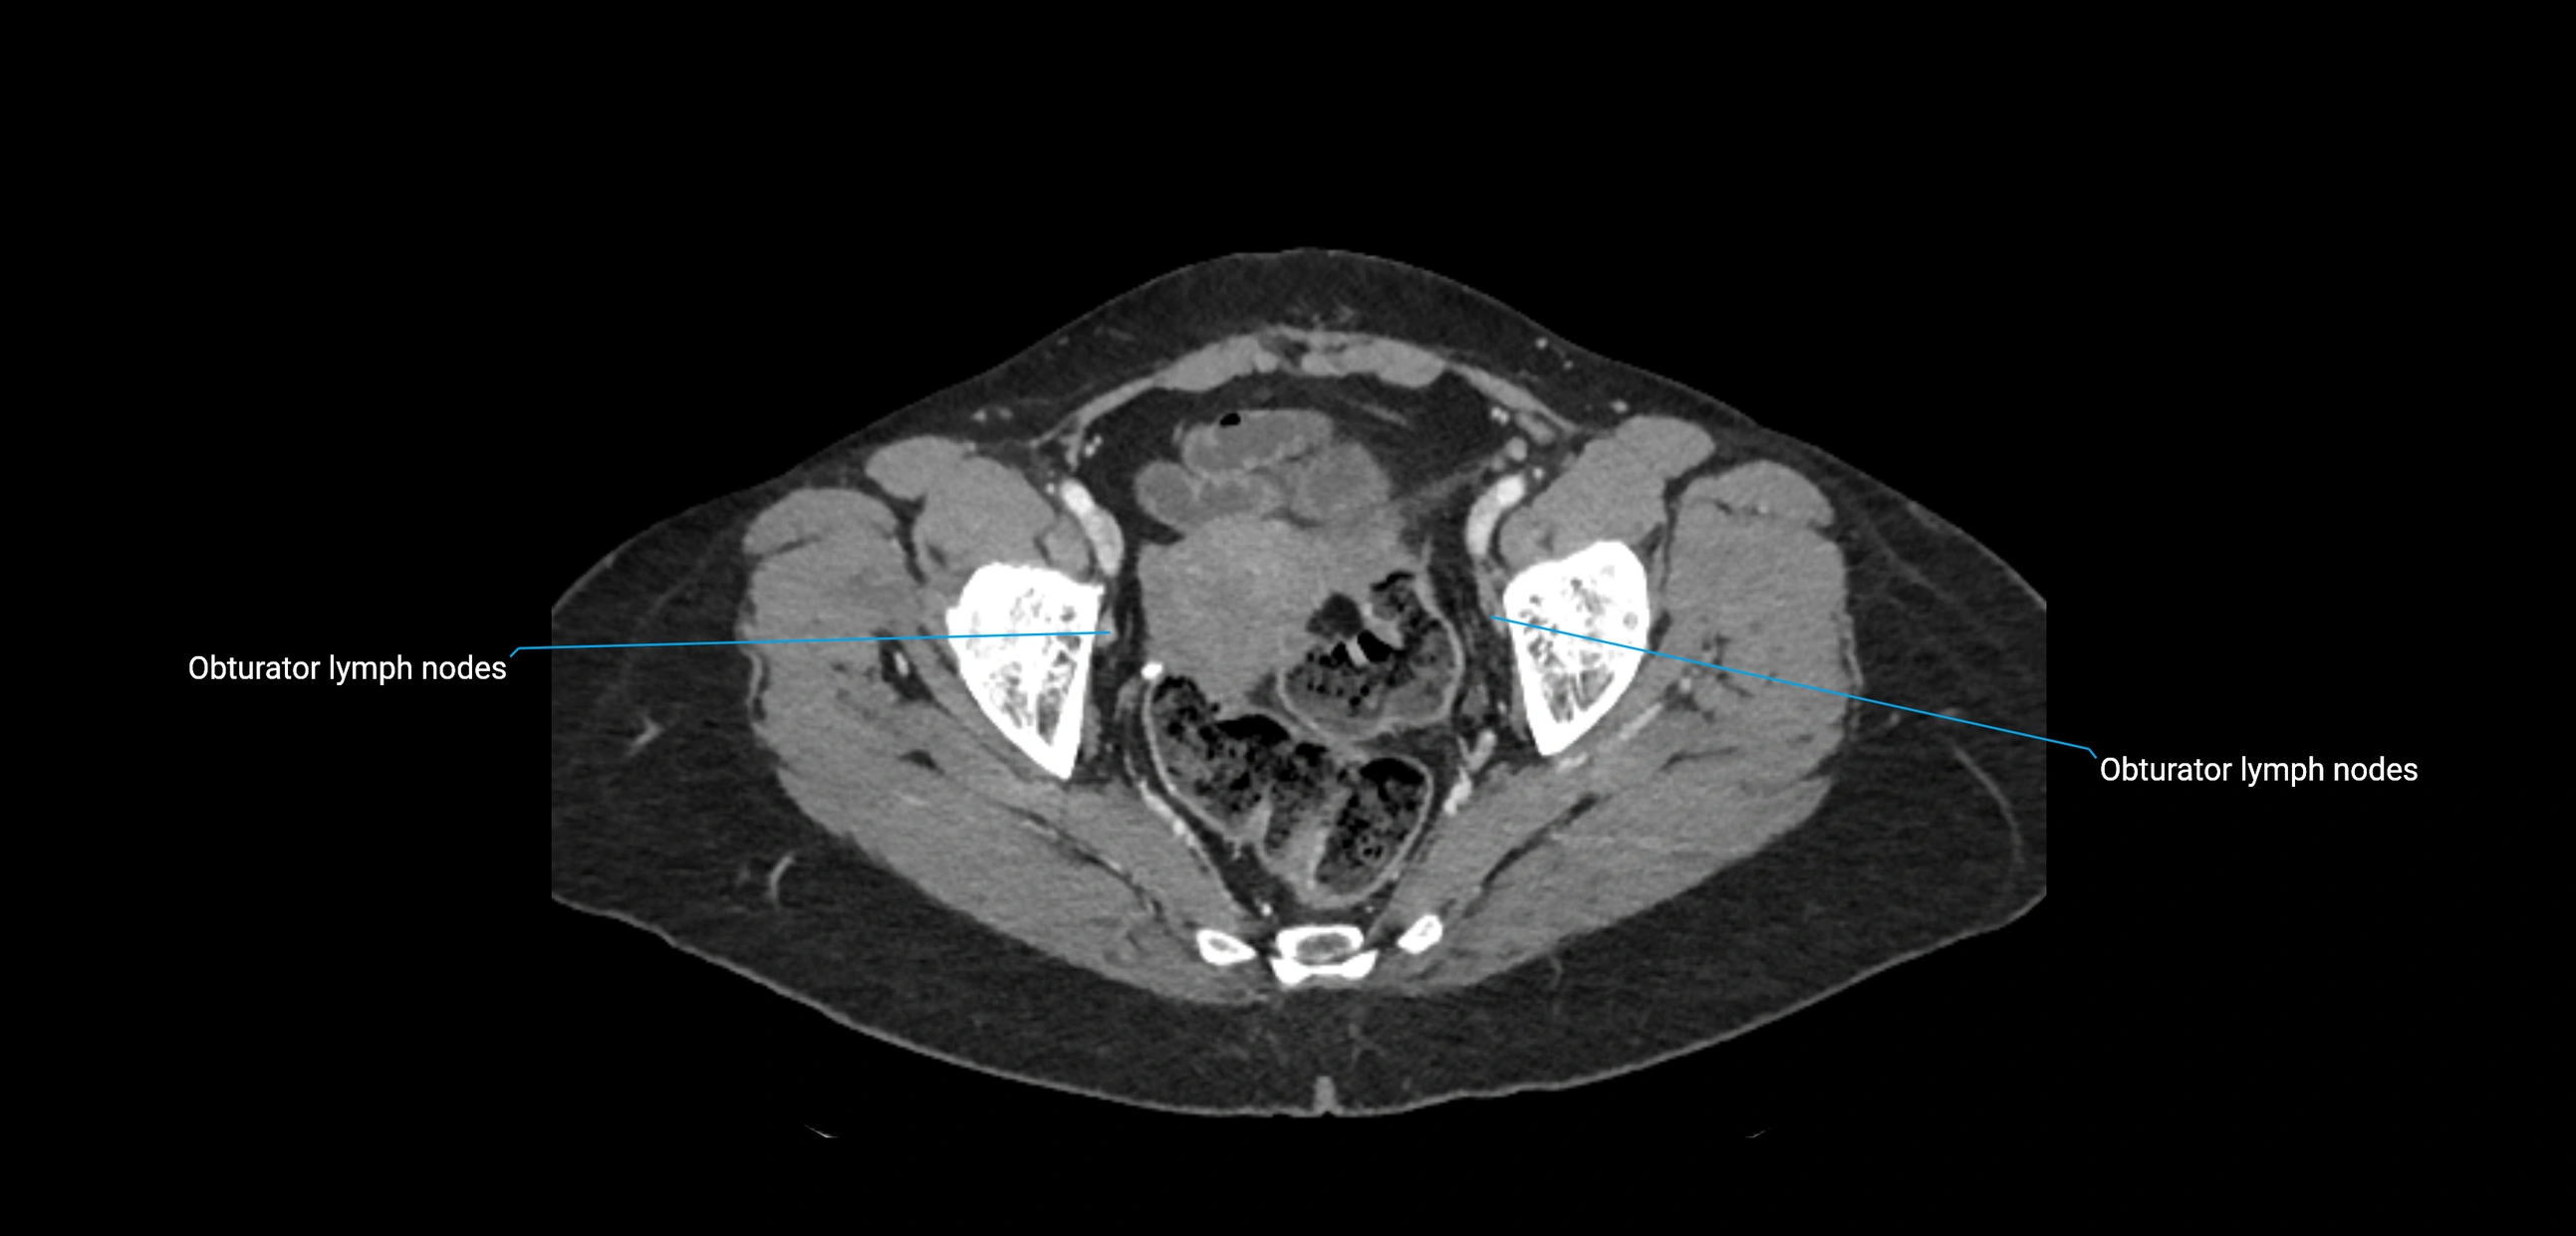

CT image

image